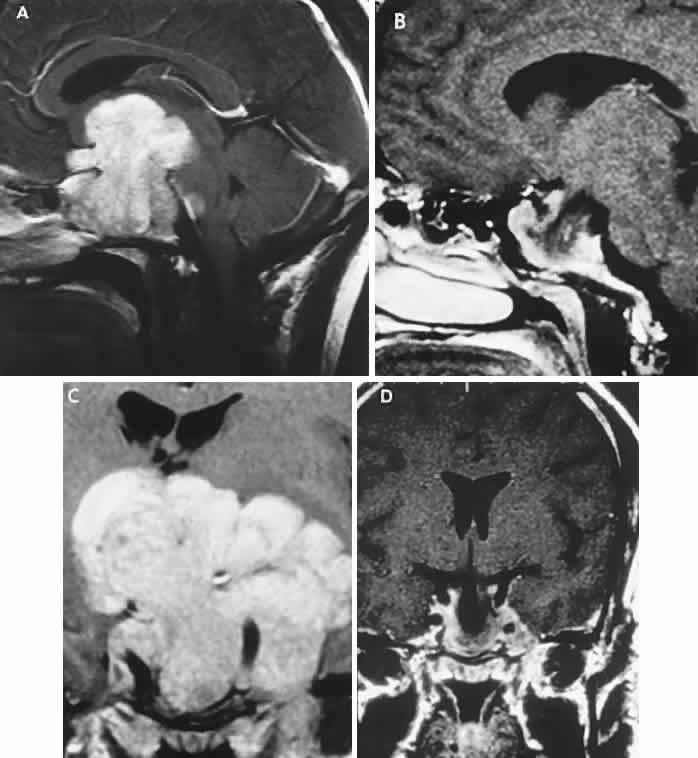

The absence of field defects, for example, in patients undergoing evaluation for amenorrhea, galactorrhea, or sellar enlargement incidentally discovered, does not imply the absence of an adenoma. Obviously, patients with microadenomas, that is, confined within the sella, do not have field defects. From a study24 of 50 cases of pituitary adenomas with chiasmal syndrome, it was concluded that visual disturbance occurs when the chiasm is displaced approximately 10 mm upward (see also Volume 2, Chapter 4, Fig. 6). The modern management of pituitary adenomas should involve several disciplines: current neuroradiologic studies detect microadenomas and provide precise delineation of gross morphology and status of neighboring structures, and mixed MRI signals suggest new or old hemorrhage, cysts, and so forth (Fig. 2); radioimmunoassay techniques assay PRL and other endocrine levels; oral neuropharmacologic agents, such as bromergocryptine, provide a “medical adenomectomy” for hyperprolactinemia and acromegaly; transsphenoidal surgery, including high-illumination microscopical procedures, televised radiofluoroscopic monitoring, and infection control, has all but replaced transcranial approaches; immunohistochemistry techniques have replaced the anachronistic tinctorial designations (e.g., chromophobe, basophilic) with a functional classification.

Fig. 2. Large prolactinoma. Original vision in the right eye (RE) was 8/200, left eye (LE) 1/200, with serum prolactin of 26,000 ng/ml and galactorrhea. Four months of bromocriptine reduced prolactin to 661 ng/ml, vision improved to RE 20/40, LE 20/50. At 3 years, vision was as follows: RE 20/30, LE 20/20; prolactin was 25.9 ng/ml. Enhanced magnetic resonance imaging. Sagittal (A) and coronal (C) images at diagnosis. Sagittal (B) and coronal (D) images at 2-year follow-up, showing dramatic shrinkage of the mass.

With the advent of the ergot-derived dopamine agonist bromocriptine, there is a pharmacologic alternative (or adjunct) to surgery for prolactinomas. Bromocriptine (2-bromo-alpha-ergocryptine) is representative of a class of ergot derivatives that, since the early 1970s, have been known to inhibit pituitary gonadotropic function, reduce PRL secretion, and diminish the size of pituitary tumors (see Fig. 2). Such ergot derivatives are structurally related to dopamine, a PRL-inhibitory factor elaborated by hypothalamic dopaminergic neurons. It is likely that bromocriptine acts in two ways: dopamine turnover in tubero-infundibular neurons is depressed, thereby increasing hypothalamic dopamine; dopamine receptors of the pituitary are inhibited, reducing both spontaneous PRL secretion and the release of PRL provoked by thyrotropin-releasing hormone. At any rate, bromocriptine decreases PRL production and secretion, with resultant reduction in lactotrope size and subsequent diminution of tumor volume, often rapidly, within 1 to 2 hours of initiation of treatment.25